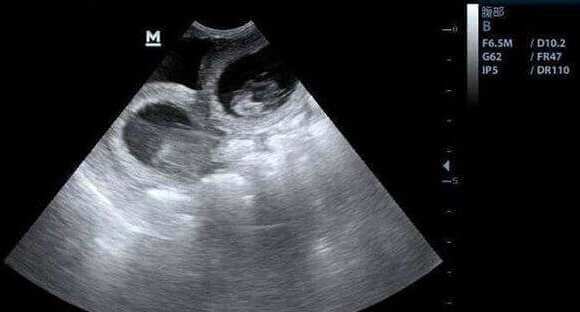

若腹痛持续加重、伴随发热、阴道出血或分泌物异常,则可能是病理性因素导致。例如,先兆流产或宫外孕在孕早期可能引发剧烈腹痛,宫外孕破裂时甚至会出现休克症状;孕中晚期,胎盘早剥、子宫破裂等严重并发症也可能表现为腹痛,需紧急处理。此外,泌尿系统感染(如膀胱炎、肾盂肾炎)或消化系统疾病(如阑尾炎、肠梗阻)也可能引发腹痛,需通过尿常规、B超等检查鉴别。